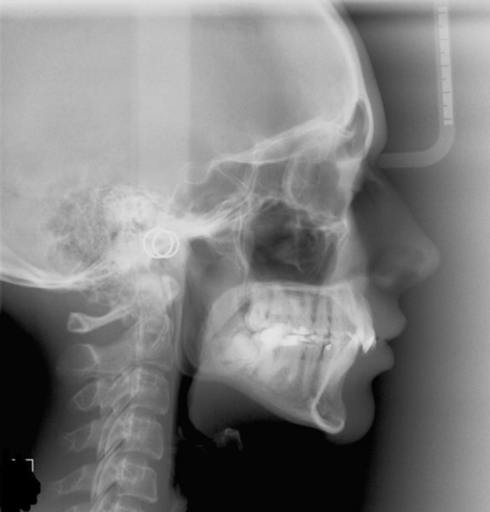

My dentist seen black spots im my jaw wants to to see oral surgeon i asked him how bad he said one of two things iys either nothing or its real bad i dont have insurance to have it checked i do have a copy of my xrays i could send them to u